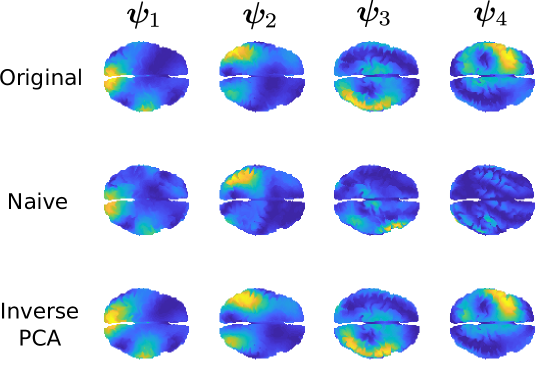

To evaluate the performances of the two approaches, we generate 100 datasets as previously detailed. The quality of the estimated th PC function is then measured with . The results are summarized in the boxplots in Figure 7, for two different signal-to-noise ratios, where the Gaussian noise has standard deviation and . In Figure 6 we show an example of a signal on the brain space corrupted with the specified noise levels.

The boxplots highlight the fact that the proposed approach provides better estimates of the PC functions (i.e. lower estimation errors ), when compared to the naive approach. Differences in the estimation error are higher in a low signal-to-noise regime, as it is for the estimation of the fourth PC function, where intuitively, the low variance associated to the PC function makes it more difficult to distinguish this structured signal from the noise component. Also surprising is the stability of the estimates of the proposed algorithm across the generated datasets, as opposed to the naive approach of reconstructing the functional observations independently, which instead returns multiple particularly unsatisfactory reconstructions. An example of such reconstructions is shown in Figure 8.